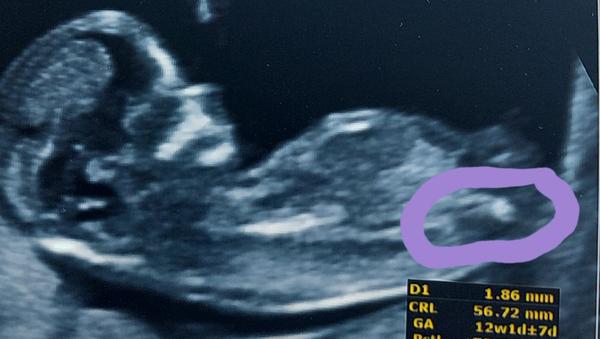

Holčička nebo chlapeček? Výsledky screeningu a tip lékaře.

Holky co myslíte ? Včerejší screening. Holčička nebo chlapeček? Lékař nám svůj typ dal.. 😀

@littlebee124 tohle mi jako pohlavní hrbolek ukázal lékař 🤷♀️

pohlavní hrbolek je podle mě daleko výš,a vypadá to na chlapečka 😀

Já bych si troufla říct, že to bude kluk, já mám holku a vypadá to jinak🙂